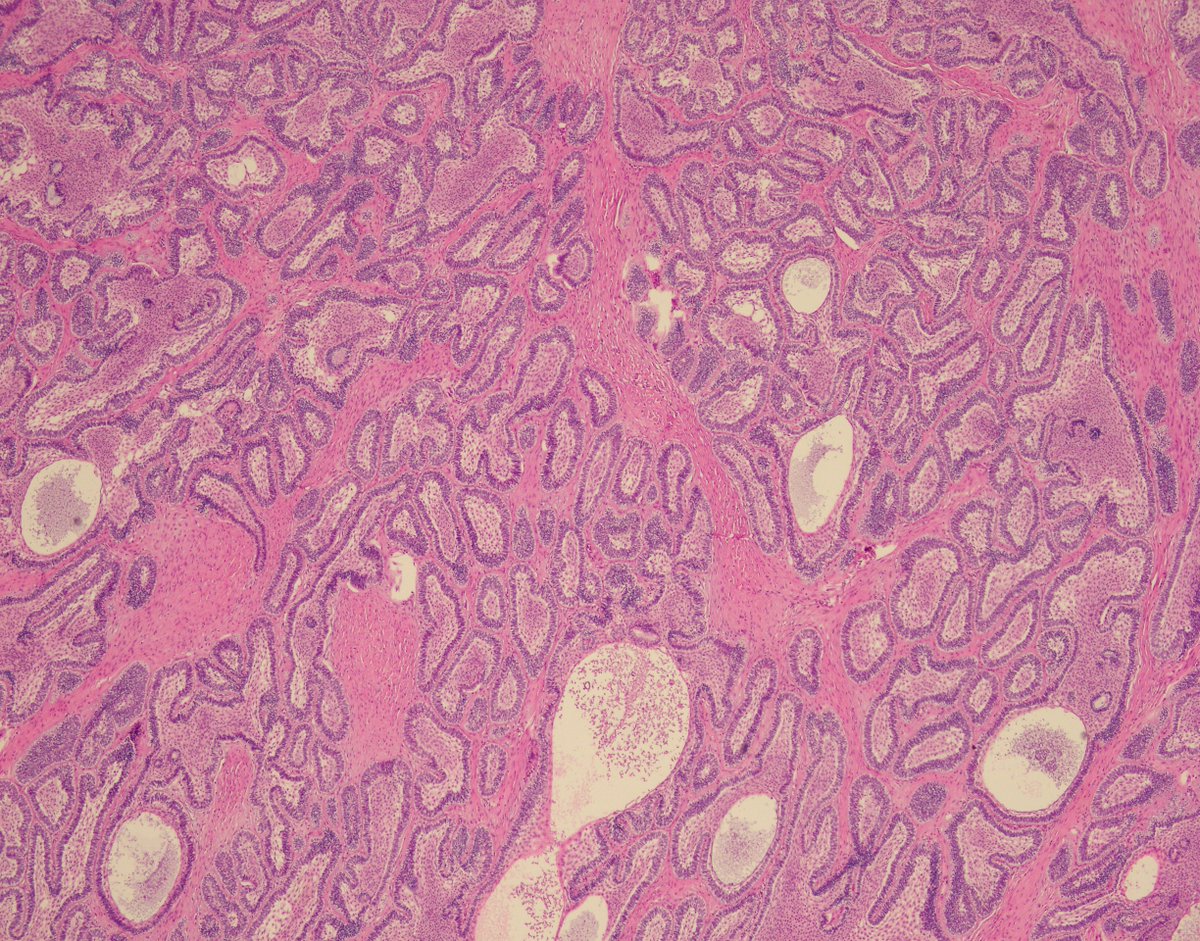

Cristina Magi-Galluzzi, M.D., Ph.D., Robert and Ruth Anderson Endowed Chair in Pathology, was installed as the 2026-2027 president of USCAP - United States and Canadian Academy of Pathology @TheUSCAP, effective April 1, 2026. Congratulations, Dr. Magi! 💚 bit.ly/4sgU4D1